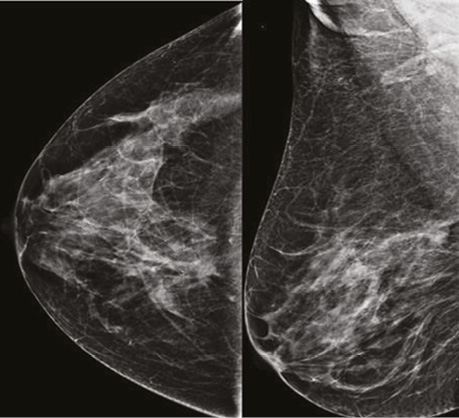

Проаналізувавши надані площинні мамографічні зображення, зазначено високу щільність паренхіми МЗ категорії ACR С з наявністю середньоінтенсивного гетерогенного ущільнення в ретромамарному просторі на 1 год правої МЗ розміром 27×21×22 мм з нечіткими променистими краями. Відзначалася наявність перинодулярної інфільтрації паренхіми, згущення структурного малюнку МЗ навколо вузлового компонента. У правій аксилярній ділянці лімфатичний вузол розміром 32×14 мм, кірково-медулярна диференціація простежується, кірковий шар нерівномірний, потовщений до 5,3 мм (рис. 1).

Рис. 1. Площинна мамографія в R-СС- та R-MLO-проєкціях. На 1 год ретромамарно — гетерогенне середньоінтенсивне вузлове новоутворення з нечіткими краями. У правій пахвовій ділянці лімфатичний вузол з нерівномірно потовщеним кірковим шаром